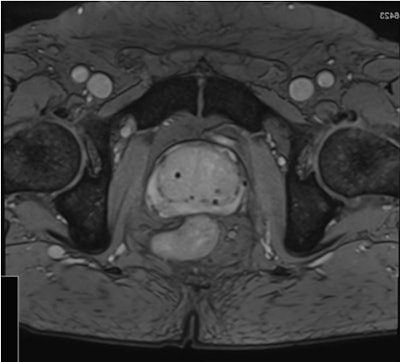

Rapid, accurate, automated segmentation algorithms are needed to handle large volumes of images that adaptive radiotherapy requires. Echo sequences optimized to better visualize the prostate can improve segmentation accuracy. Image credit: Maria Schmidt, Royal Marsden Hospital/Institute of Cancer Research. Reprinted from Int. J. Radiat. Oncol. Biol. Phys. doi: 10.1016/j.ijrobp.2017.10.020 © 2017, with permission from Elsevier.Using adaptive MRI-guided treatments, prostate patients could benefit from more extreme hypofractionation than is currently achievable with external beams, including, potentially, single fraction treatments. Reduced fractions cut the numbers of clinic visits for patients, increase patient throughput, and could improve clinical outcomes.